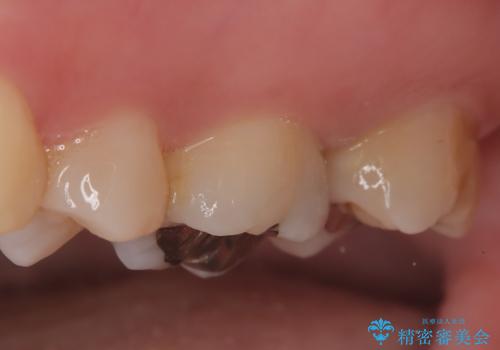

きれいな被せ物になり、患者さんにも満足していただけました。

歯牙の破折を防ぐために、セラミッククラウンにて修復しています。